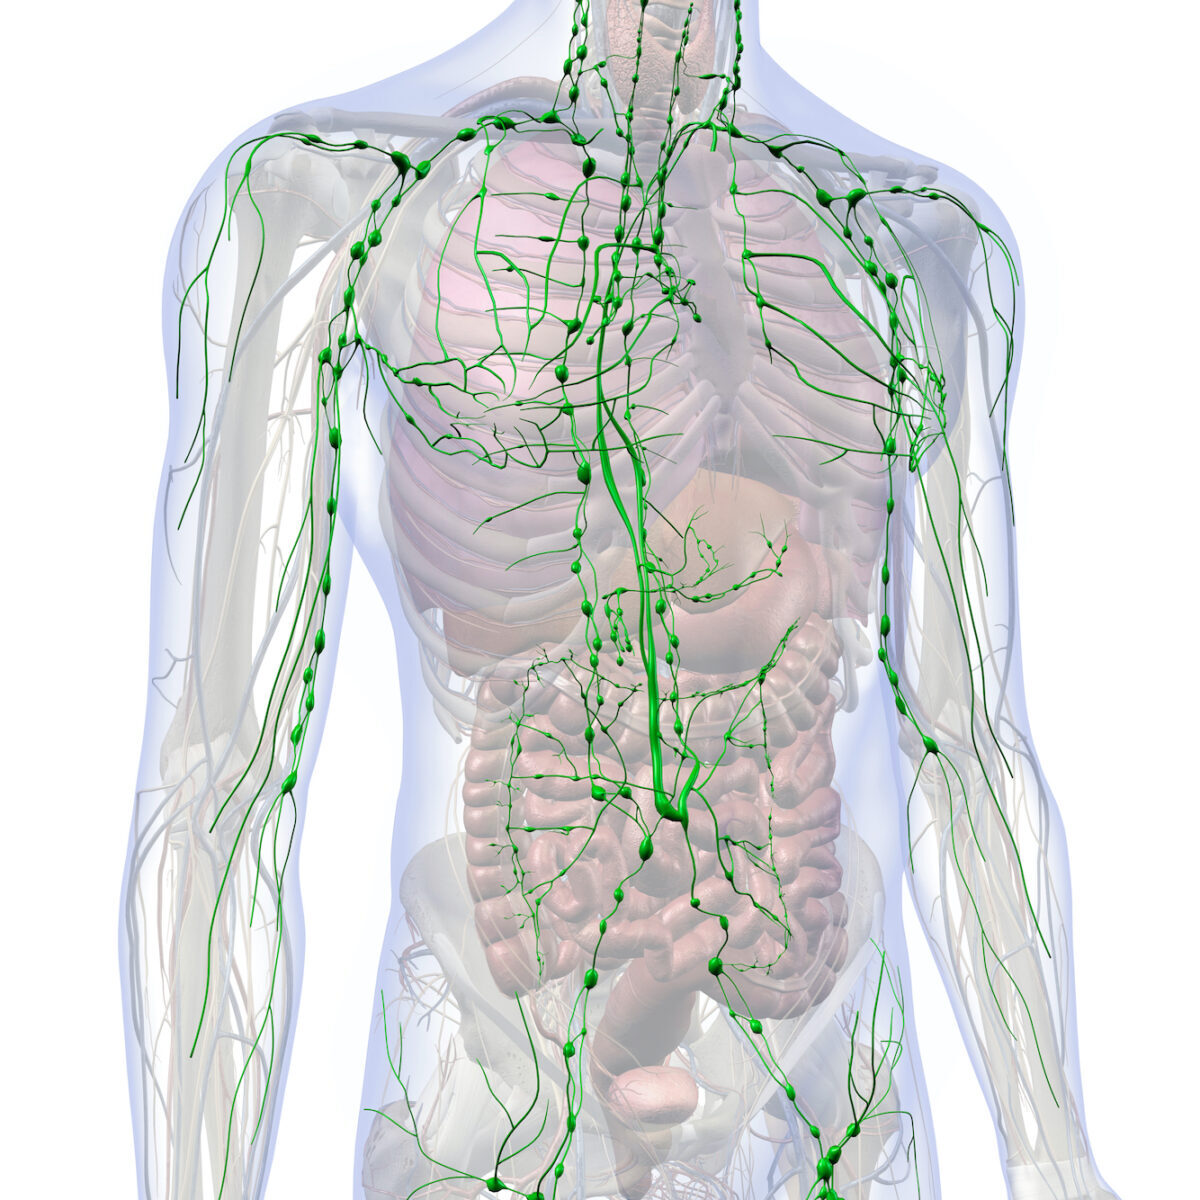

C’est pourquoi j’ai écrit le livre Lymph and Longevity. [Lymphe et Longévité, ndt.] L’ouvrage explique en quoi certains choix améliorent le flux lymphatique et atténuent l’inflammation dans tous les systèmes. Lorsque nous comprenons ce processus, nous avons beaucoup plus de chances de l’intégrer dans notre vie. Analysons donc le flux lymphatique pour voir comment optimiser tous les systèmes du corps, comme le cœur, les vaisseaux, le système immunitaire, le système nerveux et le système gastro‑intestinal.

On peut appréhender le système lymphatique de la même façon que le système cardiovasculaire, dans la mesure où il existe un fluide – la lymphe – qui est transporté vers et depuis différents endroits du corps. Cependant, contrairement au système cardiovasculaire, il n’a rien de semblable à un cœur pour le pomper. Ce sont nos mouvements et les contractions de nos muscles qui régulent principalement le flux lymphatique.

Qu’est‑ce que le flux ? Chaque système biologique a une fonction qui permet d’acheminer les nutriments essentiels, les cellules importantes et les messages chimiques, mais aussi d’évacuer les déchets, les cellules et les signaux cellulaires. Au cours de ce processus, certains fluides, cellules, protéines et graisses restent dans les tissus et doivent être éliminés par le système lymphatique. Le flux lymphatique est nécessaire pour renvoyer l’excès de liquide tissulaire vers le sang, acheminer les graisses et les protéines vers le foie et les reins, et transférer les cellules immunitaires et les messages immunitaires vers les ganglions lymphatiques. L’élément clé ici est le flux de la lymphe – qui comprend le taux et la qualité du mouvement du fluide dans tout le système.

Le système lymphatique est le lieu où se gagnent et se perdent nos batailles biologiques au quotidien. La lymphe joue un rôle dans pratiquement tous les problèmes majeurs qui peuvent survenir dans le corps. C’est pourquoi on la surnomme la « Cendrillon de la médecine » – méconnue, mais faisant tout le travail. Le système lymphatique touche tous les autres systèmes de l’organisme.

Voyons comment le système lymphatique nourrit et protège les principaux organes du corps. Son principal objectif est d’éradiquer l’inflammation chronique en éliminant les toxines, en équilibrant les fluides, et en signalant et transportant les messages dans tout le corps. Cette tâche s’effectue de manière subtilement différente pour chaque système.